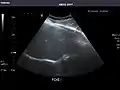

Aorta

Aorta: Visualized portions normal in caliber, 16 x 15 mm.